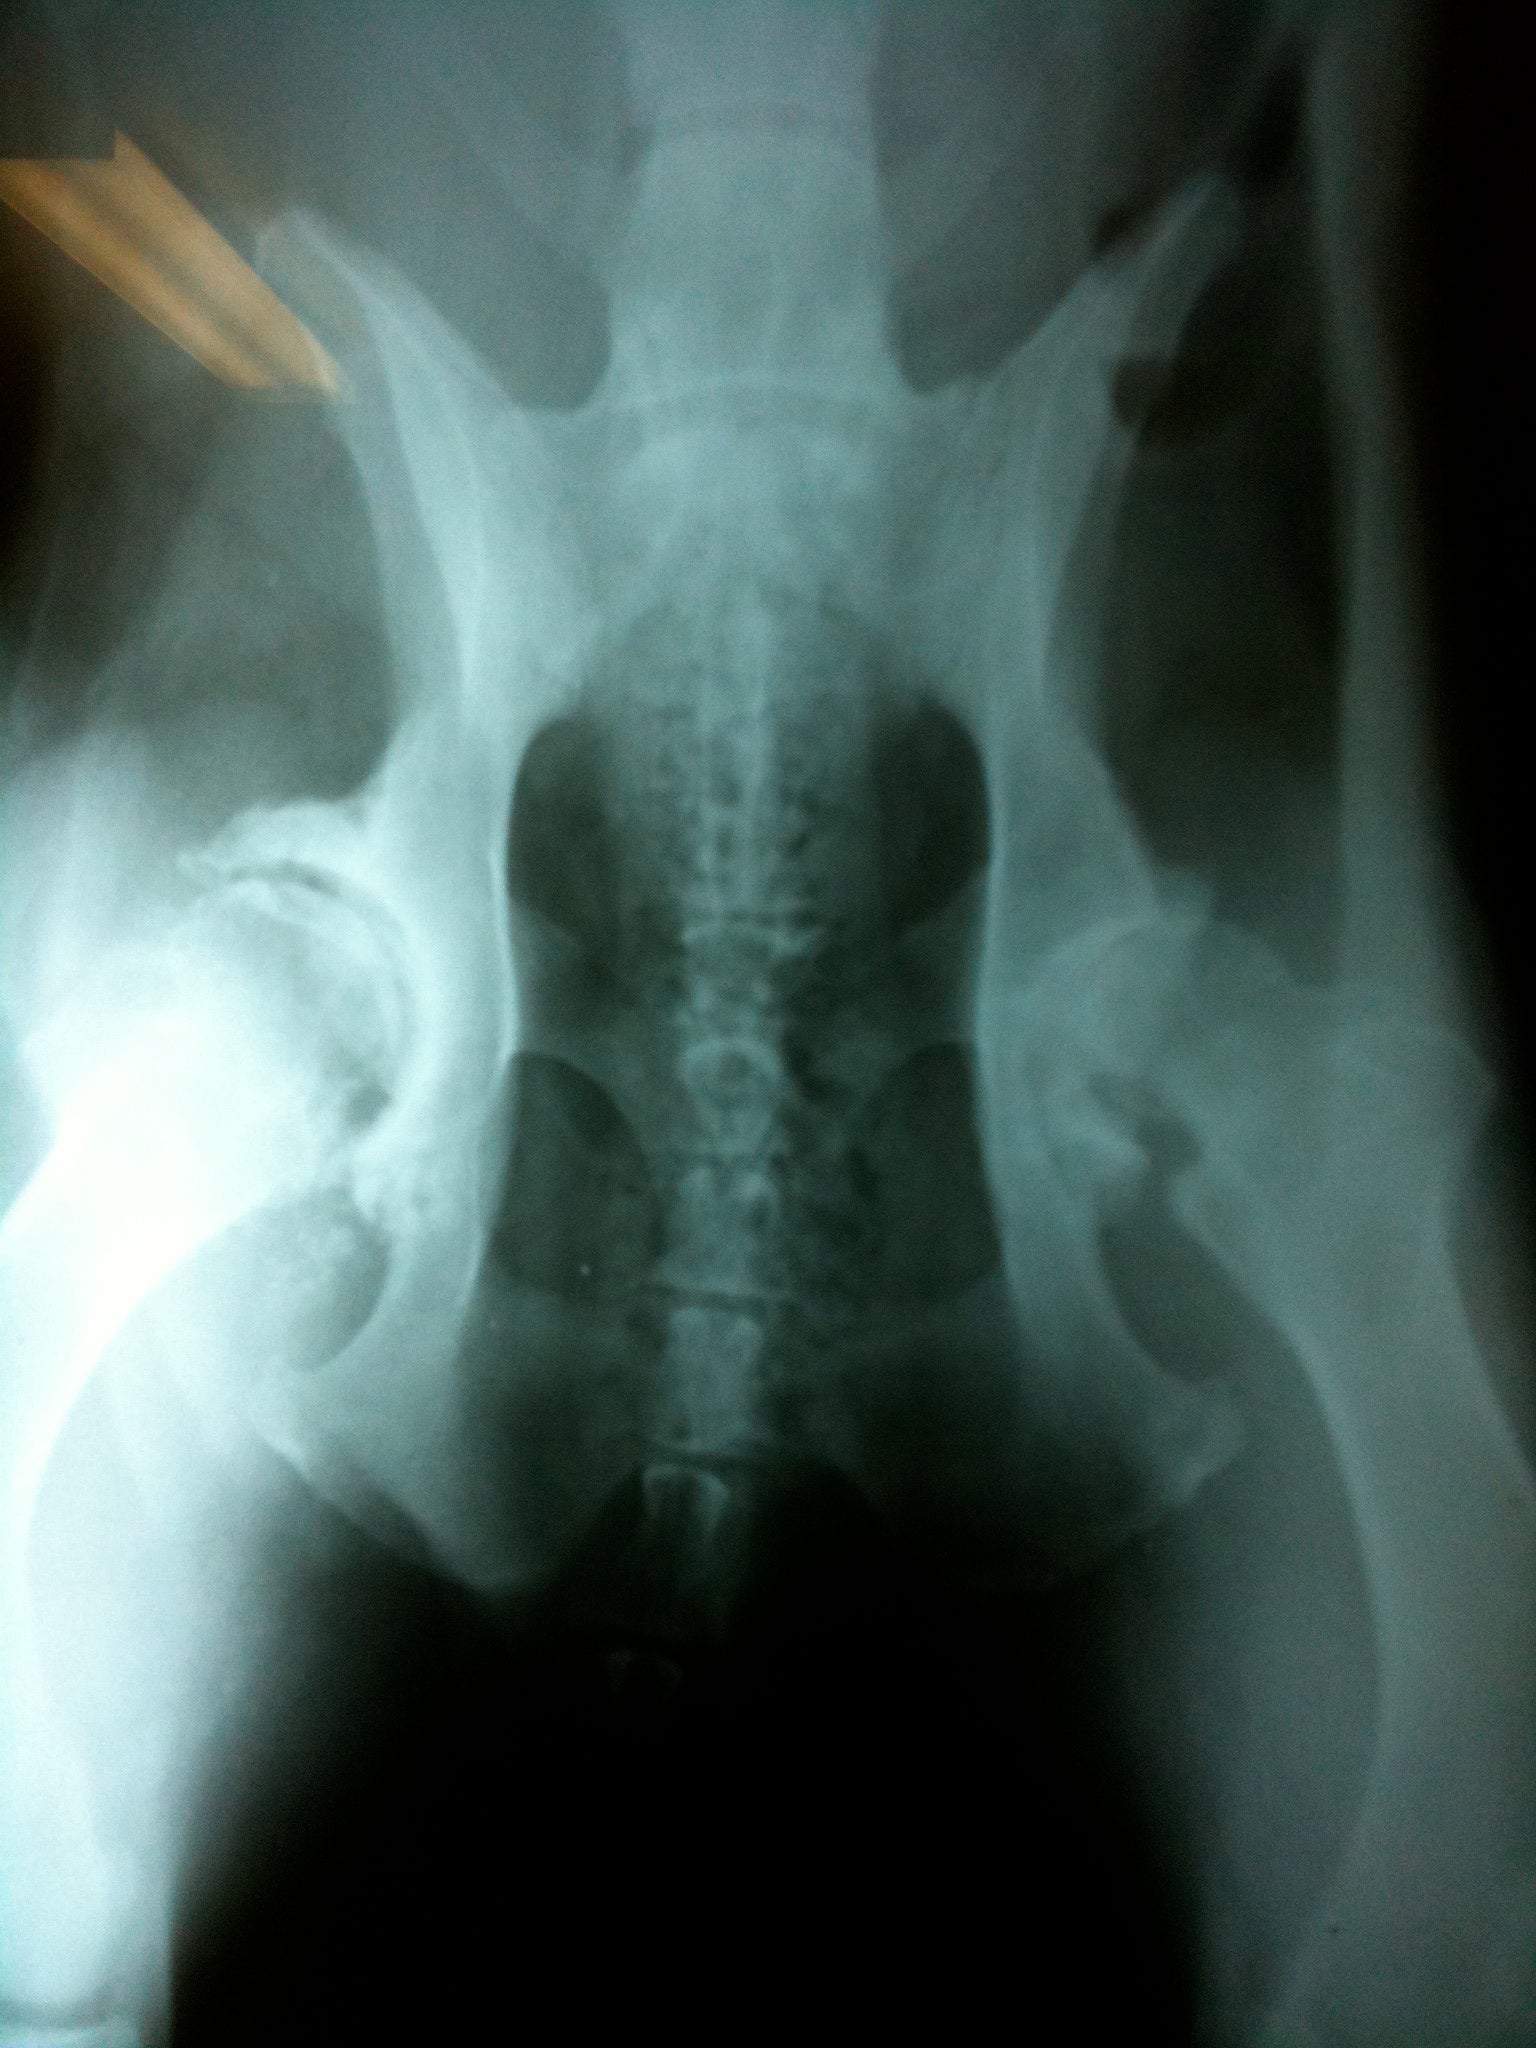

A version of this article is featured on the Embrace Pet Insurance Blog. Photo shows hip dysplasia and osteoarthritis in one of my DELTA Rescue patients.

Congenital and developmental joint malformation- hip and elbow dysplasia, etc

When a joint becomes inflamed, the immune system is called into action to reduce inflammation. If the underlying cause of inflammation is removed and adequate time is given for the body to heal, the joint may not have sustained any permanent damage. Other times, more severe damage occurs or inflammation is inadequately controlled, which starts the painful process of degenerative joint disease (DJD). DJD is a permanent remodeling of joint surfaces which limits range of motion, mobility, and overall quality of life.

Should your pet show any inability to use a limb (there are four) properly, immediately address the problem with your veterinarian. Radiographs (xrays) may be needed to determine if the joints and bones are normal or abnormal. The piece of mind that comes from finding no evidence of fracture, joint abnormality, or other significant concerns is well worth the expense.